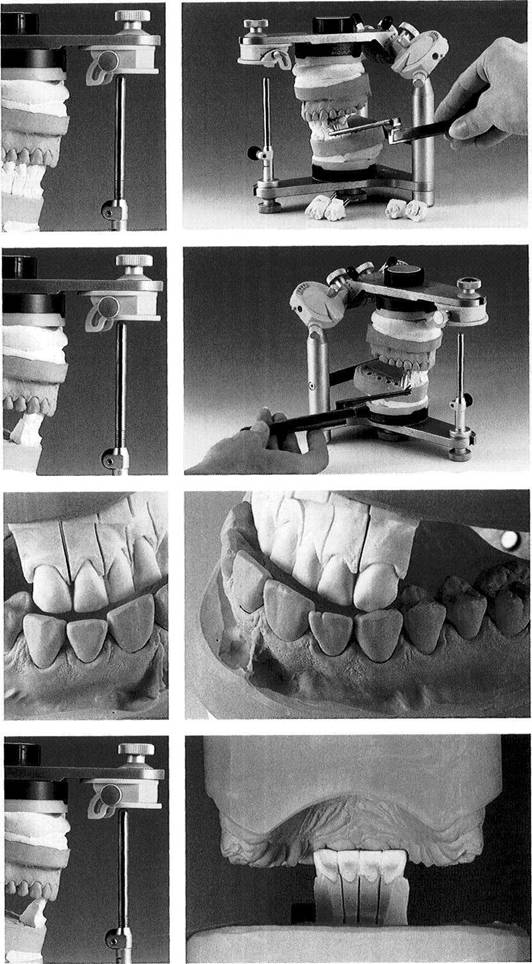

Materials for occlusal

Maxillary and mandibular casts are mounted in a relationship to the articulator corresponding to that of the natural teeth to the cranium and joints. The segmented mandibular cast with removable teeth has also been mounted in centric and thus is interchangeable with the solid mandibular cast. Strips of shim stock cut to the width of a premolar are used to test the occlusal con­tacts.

All of the posterior teeth and at least the lower canines should be removable as individual segments.

Centric occlusion

The segmented mandibular cast has been substituted for the solid mandibular cast.

The upper member of the articula­tor is closed to the first occlusal contact.

Preliminary inspection suggests that occlusal equilibration by selec­tive grinding could be accom­plished only with considerable loss of tooth structure in the molar region.

651 Lingual view of the teeth in centric occlusion